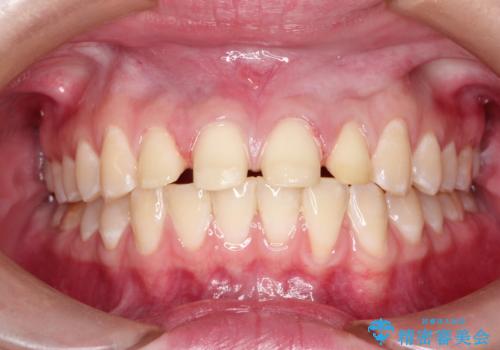

- 前歯をきれいにしたいとのご希望がありました。

生まれつき歯の色が白濁しているところや、黄色くなっているところがあり、セラミッククラウンに審美的改善を行うこととしました。

ご自身の歯を削る必要がありましたが、セラミッククラウンを装着することで、審美的改善ができました。